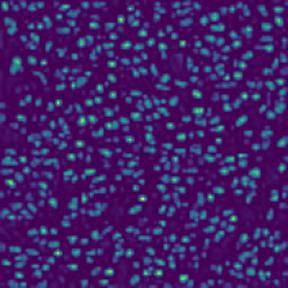

Microscopic image segmentation is a challenging task, wherein the objective is to assign semantic labels to each pixel in a given microscopic image. While convolutional neural networks (CNNs) form the foundation of many existing frameworks, they often struggle to explicitly capture long-range dependencies. Although transformers were initially devised to address this issue using self-attention, it has been proven that both local and global features are crucial for addressing diverse challenges in microscopic images, including variations in shape, size, appearance, and target region density. In this paper, we introduce SA2-Net, an attention-guided method that leverages multi-scale feature learning to effectively handle diverse structures within microscopic images. Specifically, we propose scale-aware attention (SA2) module designed to capture inherent variations in scales and shapes of microscopic regions, such as cells, for accurate segmentation. This module incorporates local attention at each level of multi-stage features, as well as global attention across multiple resolutions. Furthermore, we address the issue of blurred region boundaries (e.g., cell boundaries) by introducing a novel upsampling strategy called the Adaptive Up-Attention (AuA) module. This module enhances the discriminative ability for improved localization of microscopic regions using an explicit attention mechanism. Extensive experiments on five challenging datasets demonstrate the benefits of our SA2-Net model. Our source code is publicly available at \url{https://github.com/mustansarfiaz/SA2-Net}.